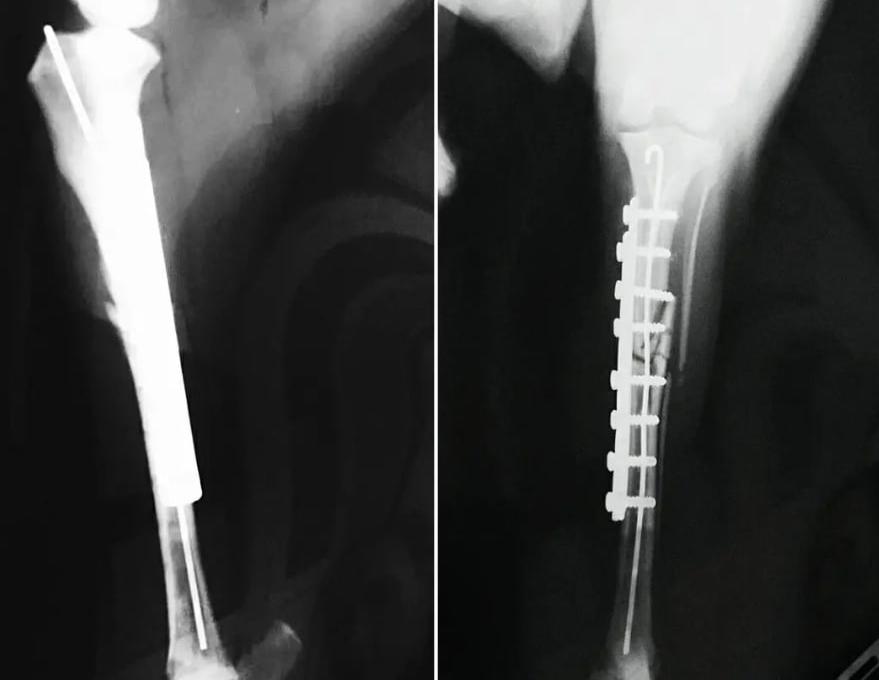

Ветеринарная клиника Ветдопомога — это место, где профессиональная медицина сочетается с искренней эмпатией к каждому четвероногому пациенту. Команда клиники воспринимает свою работу не просто как оказание услуг, а как миссию — быть рядом с владельцами в самые ответственные моменты, обеспечивая животным долгую и здоровую жизнь. Здесь одинаково заботливо относятся как к домашним питомцам, так и к бездомным животным, ведь в основе ценностей учреждения лежит убеждение, что каждая жизнь заслуживает спасения и заботы. Клиника предлагает полный спектр помощи — от плановых осмотров, вакцинации и чипирования до сложных хирургических вмешательств и комплексного лечения внутренних болезней.

Благодаря современному оборудованию и высоким стандартам стерильности, врачи проводят точную диагностику и эффективную терапию, всегда оставаясь на связи с владельцами для предоставления бесплатных консультаций и советов по правильному содержанию животных. Специалисты учреждения не боятся сложных случаев, применяя свой многолетний опыт, чтобы даже в самых трудных ситуациях вернуть хвостикам радость жизни, а их хозяевам — спокойствие. Каждый визит в «Ветдопомогу» — это история о доверии, где пациент ощущает тепло человеческих рук, а владелец получает профессиональную поддержку и уверенность в качестве лечения своего друга.